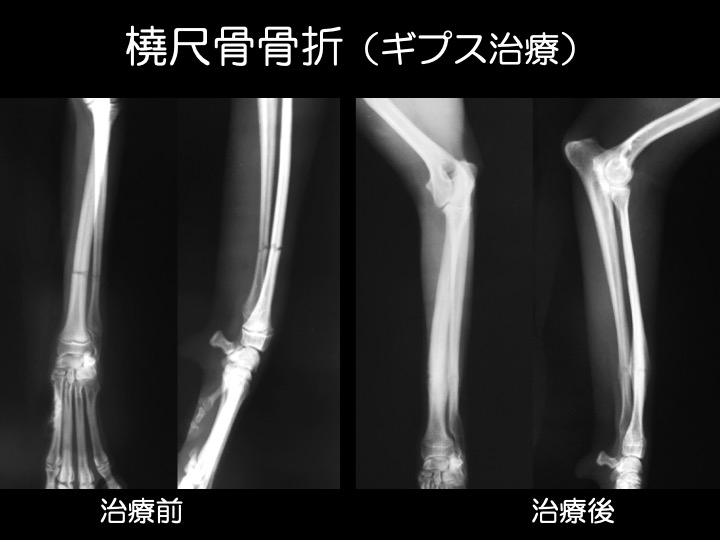

ギプス治療例

・骨折による“骨のズレ”が小さい場合、ギプスによる治療が可能です。多くの場合、全身麻酔を必要としないため、動物の負担も少なく済みます。

【ギプス(外固定)】

・骨折による骨のズレが小さい場合などが適応となります。

・手術前後の一時的な固定として使用されることもあります。

・多くの場合、全身麻酔を必要としません。